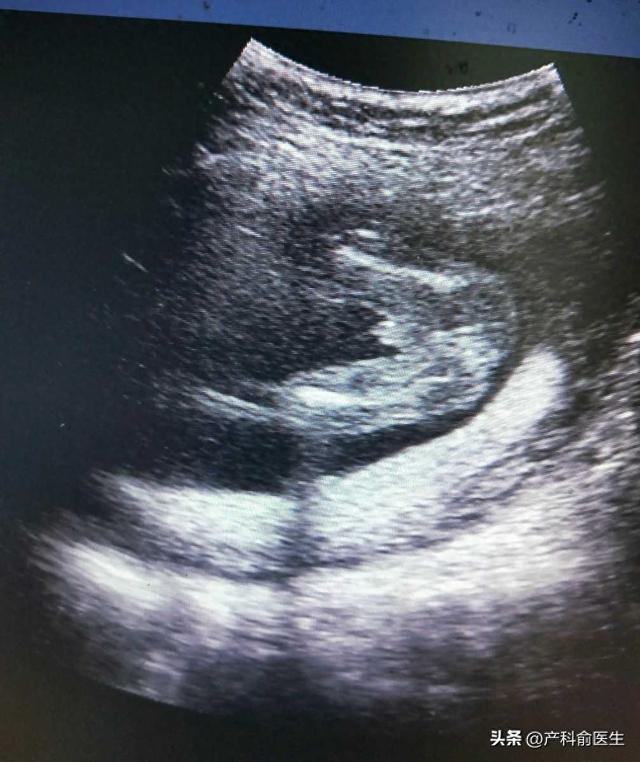

怀孕16周怎么辨别男女(超声医师会暗示胎儿的性别吗产科医生告诉你真相)

很多孕妈在做产检时,都会有一个共同的心愿:想知道肚子里宝宝的性别。于是,在超声检查时,大家常常会留心观察医生的言行,甚至觉得医生的某些“词汇”就是在暗示宝宝是男孩还是女孩。那真的是这样吗?...